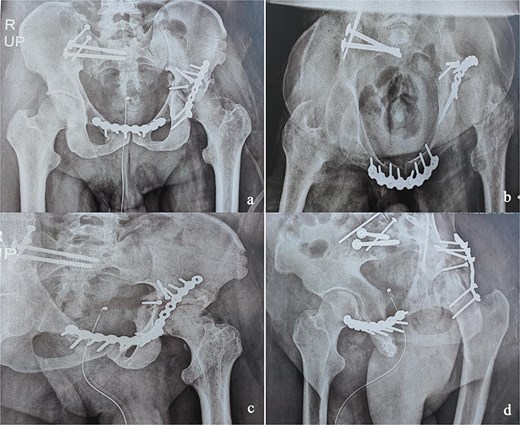

At the 10-month follow-up, the patient showed signs of left hip osteoarthritis with functional deterioration, for which a total ceramic-on-ceramic hip arthroplasty was performed, using a screw-fixed structural graft at the acetabulum (Fig. 3). At the final follow-up, 36 months postoperatively, the patient was walking unaided with the use of an anti-equinus splint on the left foot. The HHS was 85 and Majeed score was 86 [6, 7]. X-rays showed complete bone healing of all fractures and the acetabular graft. It should be noted that, during follow-up, the patient had a right femoral fracture that was successfully treated with a gamma nail (Fig. 4). Written informed consent were obtained from the patient.

(a and b) Inlet and obturator oblique views showing a left hip osteoarthritis with subluxation of the femoral head. (c) Anteroposterior pelvic X-ray: left total hip arthroplasty, acetabular bone reconstruction with a screwed structural bone graft.